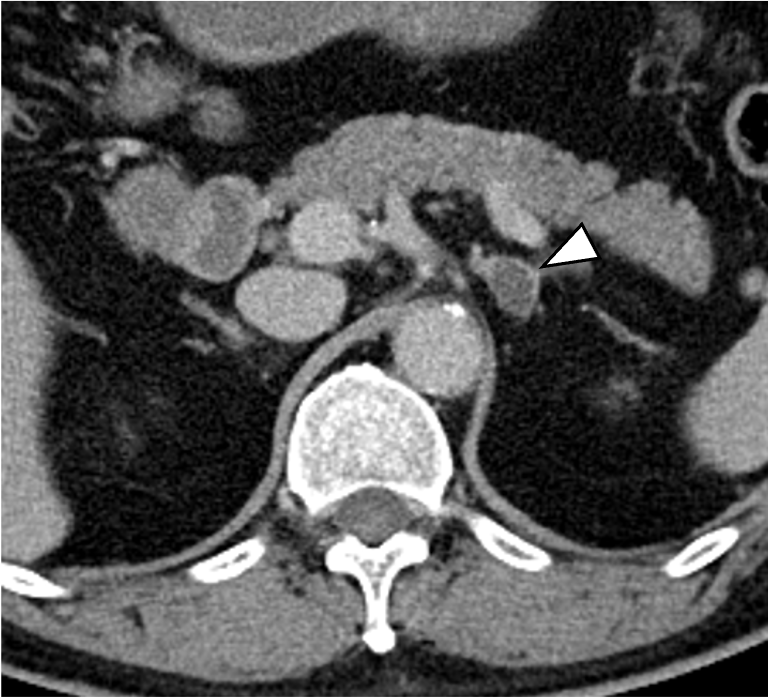

高血圧, 低K血症の精査で左副腎腫瘤が指摘され, 負荷試験の結果, 原発性アルドステロン症の診断となった, 副腎静脈サンプリング前に,プランニング目的のCTが施行された, その後の副腎静脈サンプリングでは, 左副腎からの片側性のアルドステロン過剰分泌が認められ, 手術の方針となった.

原発性アルドステロン症は, 治癒可能な二次性高血圧であり, 本態性高血圧より脳・心血管, 腎合併症の頻度が高く, その診断および治療の重要性が指摘されている, 片側性のアルドステロン症の場合, 外科的切除によりアルドステロン過剰の正常化, 高血圧および臓器障害の改善・防止が期待できる, このため, 手術が考慮される場合には副腎静脈サンプリングによる機能的局在診断を行う, 原発性アルドステロン症診療ガイドライン20211)では, この副腎静脈サンプリングの成功率を向上させる方法の一つとして, ダイナミックmulti-detector row CT(MDCT)が推奨されている, MDCTでは, 横断像やMPR(Multi planar Reconstruction)を用いて, 副腎静脈の走行やvariationの確認などを行うが, これに加え当院では,仮想透視画像を作成し, 右副腎静脈の下大静脈開口部のレベルや, 副肝静脈との位置関係など, 立体的な解剖学的把握を行っている, その結果, サンプリング時に, スムーズかつ的確なカテーテル操作が可能となる.

本検査における後期動脈相は, 右副腎静脈と下大静脈との合流部, また左副腎静脈と下横隔静脈, 腎静脈との合流部の形態評価が求められる重要な撮影時相である. そのため30sec注入時間固定法とbolus tracking法の併用を行い, 腹部下行大動脈において+100HUのCT値上昇をトリガーとし, 20secのdelay timeにて後期動脈相の撮影を行っている. その後の門脈優位相は, トリガーから40secの撮影とし, 主に副肝静脈と下大静脈との合流部の形態評価が目的とされる. 造影コントラスト向上のため. 可能な限り低管電圧撮影が行えるよう留意している. なお, 本症例は, 造影剤量がプロトコルより少ない症例であったが, 低管電圧撮影や後期動脈相の最適な撮影タイミングにより, 副腎静脈を良好に描出し得た.